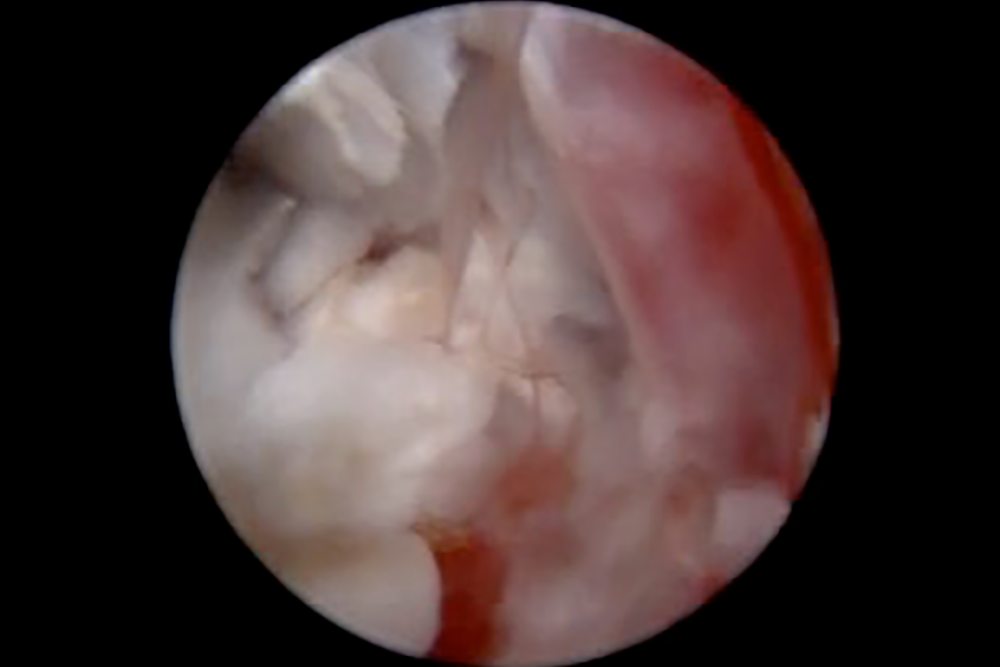

ビデオオトスコープ(耳の内視鏡)は耳用の内視鏡を用いた検査・治療法で、視覚的に優れた検査を実施できるだけでなく、耳道内の洗浄および鉗子やレーザーを用いた耳科手術を実施することができます。

施術内容は、外耳、鼓膜、中耳の観察及び洗浄 ・耳道内異物の除去 ・耳道内腫瘤(しこり)の検査及び切除で、施術の内容によっては当院で診察をしている動物皮膚科コンサルタントの大隅先生と実施します。